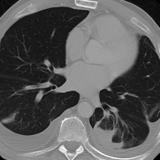

Rounded atelectasis case 1 CT

Date: 01/13/2008

Views: 3395